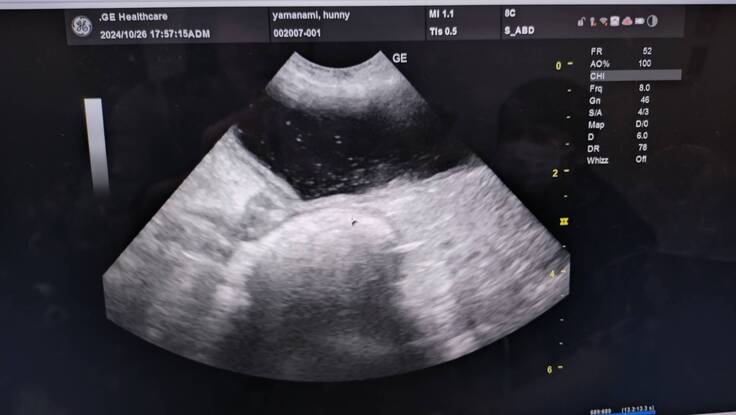

エコー写真→キラキラ白く写っているのが菌、脂肪や結石様のもの浮遊物